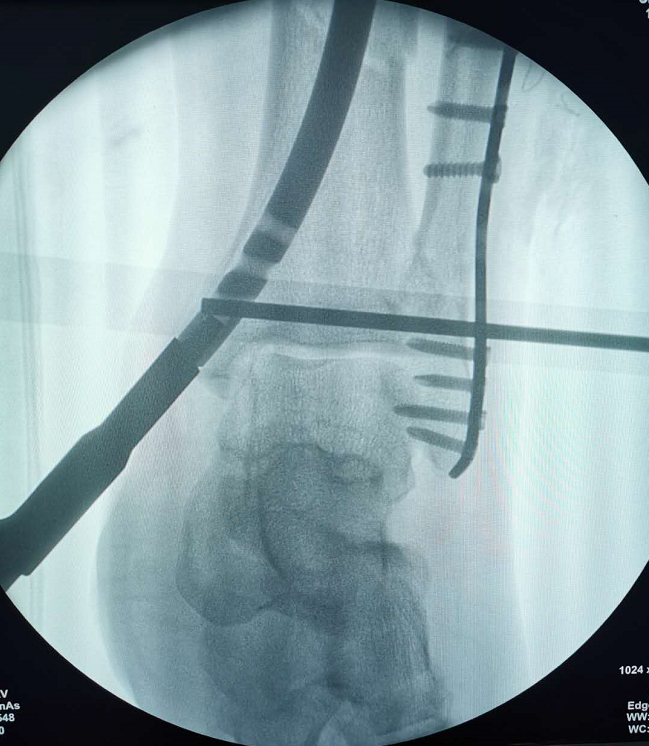

近期,我院骨科四病区刘京升主任团队完成了一例胫腓骨远端骨折合并足部多发骨折患者的治疗,其中应用的胫骨逆行髓内钉技术属全省首例,手术由刘京升主任医师、王凯副主任医师和冯凯医师共同完成。

小腿远端腓骨骨折治疗多采用切开复位钢板内固定,胫骨骨折可选用MIPPO技术钢板固定、胫骨顺行髓内钉及胫骨逆行髓内钉技术,其中MIPPO技术因患者软组织条件差术前消肿时间过长,顺行髓内钉因骨折线位置较低髓内钉远端把持力不足,同时会一定程度影响膝关节活动。而胫骨逆行髓内钉技术作为国内逐渐发展起来的新技术,在处理胫骨远端骨折时具有软组织损伤小、复位及固定简易等优势,十分适合本症状患者。